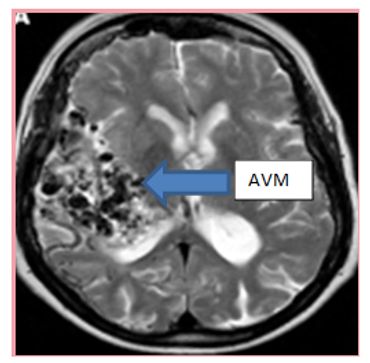

An arteriovenous malformation, or AVM is an abnormal tuft of vessels between arteries and veins without intervening capillary network. AVMs can occur in different organs of the body, but brain AVMs are the most problematic.

મગજના એમ.આર.આઈ. એક આદર્શ તપાસ પધ્ધતિ છે. જોકે ડીજીટલ સબસ્ટ્રેકશન એન્જીયોગ્રાફી ૮મકબ૯ એ.વી.એમ. ના નિદાન માટે ગોલ્ડ સ્ટાન્ડર્ડ અને ફરજીયાત રહે છે. જયારે રકતસ્ત્રાવ (હેમરેજ) થતો હોય તેવા કિસ્સાઓમાં એ.વી.એમ. કેટલીકવાર ઈન્ટ્રા સેરીબ્રલ રકતસ્ત્રાવ ૮યહજ૯ દ્વારા સંપૂર્ણપણે અસ્પષ્ટ થઈ જતું હોય છે તેવા સંજોગોમાં ડીજીટલ સબસ્ટ્રેકશન એન્જીયોગ્રાફી ૮મકબ૯ ખુબજ કામમાં આવે છે.

MRI brain is an ideal screening modality. However AVMs can be missed on non-invasive imaging and for final diagnosis and for evaluation before treatment Digital Subtraction Angiography (DSA) is mandatory. In cases when bleeding has occurred, the AVM can sometimes be completely obscured by intracerebral bleeding.